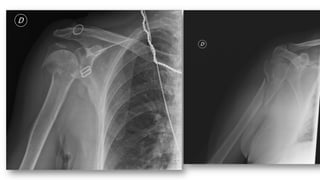

FRACTURA HUMERO

• 5% de las fracturas del adulto, 75% en 1/3 superior

• Más frecuentes en ancianos (osteoporosis)

• Tratamiento:

• Conservador: cuello quirúrgico con impactación (ancianos)

• Quirúrgico: el resto

• Complicaciones

• Seudoartrosis

• Consolidación defectuosa

• Necrosis avascular

• Lesión nerviosa ó vascular

• Rigidez-capsulitis.

• Fx diáfisis: más frecuente en jóvenes o ancianos con fx patológica

• Clasificación de Neer: relación entre troquín, troquíter,

segmento articular y diáfisis

• Divide las fracturas en función de los desplazamientos de

estos segmentos

• FX desplazada: tiene 2, 3 o 4 segmentos, fractura-luxación,

fractura articular

• Separación >1cm o ángulo >45º